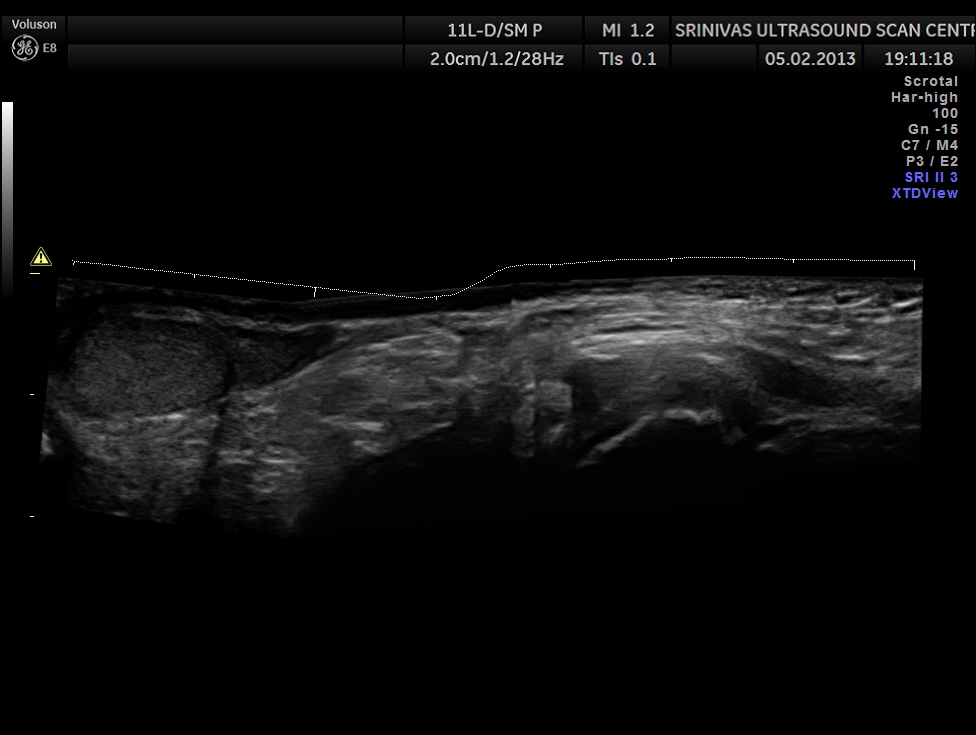

This was a 11 year old boy referred for evaluation of left inguinal swelling on and off.

The clinical diagnosis was bubunocele.